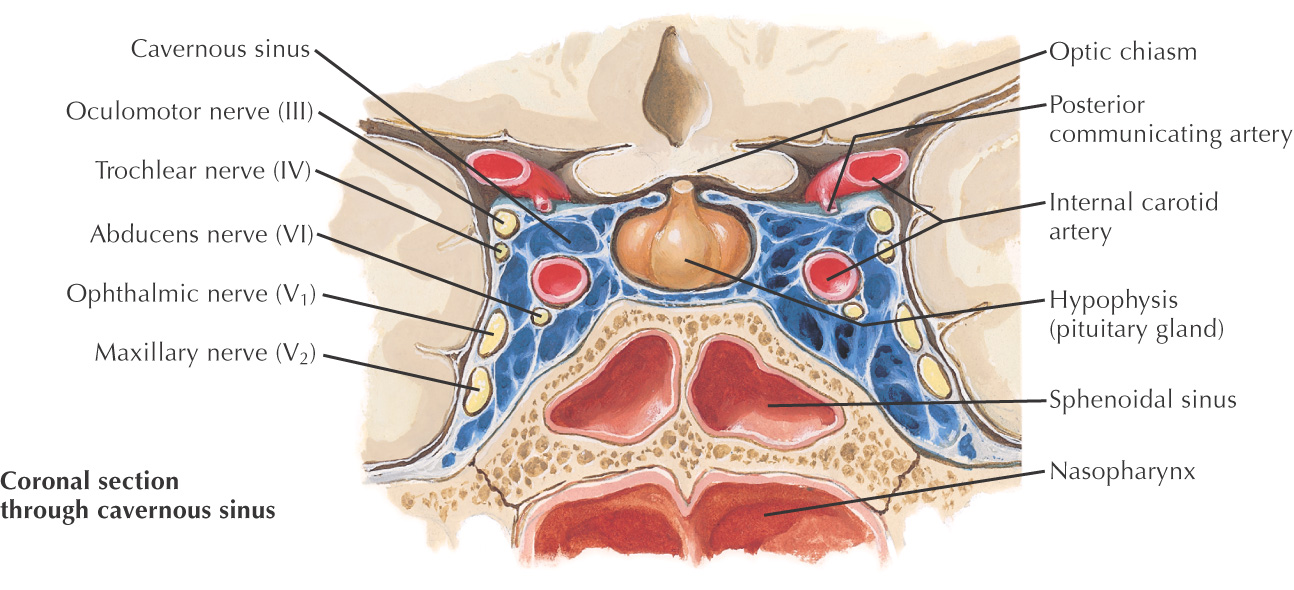

• Superior: hypophyseal fossa, pituitary gland, optic chiasm

• Inferior: nasopharynx, pterygoid canal

• Lateral: cavernous sinus, internal carotid artery, cranial nerves III, IV, V1, V2, and VI

• Sphenoid: rare, but in this location can result in problems with the pituitary gland, cavernous sinus syndrome, and meningitis